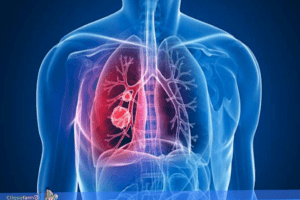

Tuberculose

A tuberculose é uma doença infecciosa e transmissível, causada pela bactéria Mycobacterium tuberculosis, também conhecida como bacilo de Koch. A doença afeta principalmente os pulmões, embora possa acometer outros órgãos. A forma extrapulmonar, que afeta outros órgãos que não o pulmão, ocorre mais frequentemente em pessoas vivendo com HIV, especialmente aquelas com comprometimento imunológico.

A transmissão acontece por via respiratória, pela eliminação de aerossóis produzidos pela tosse, fala ou espirro de uma pessoa com tuberculose ativa, sem tratamento. A tuberculose não é transmitida por objetos compartilhados. Os sintomas incluem tosse por três semanas ou mais, febre vespertina, suor noturno e emagrecimento.

O tratamento dura no mínimo seis meses e pode ser feito com o uso de quatro medicamentos: rifampicina, isoniazida, pirazinamida e etambutol. Segundo a Organização Mundial da Saúde (OMS), todos os dias mais de 4,1 mil pessoas perdem a vida devido à tuberculose e cerca de 30 mil adoecem no mundo.